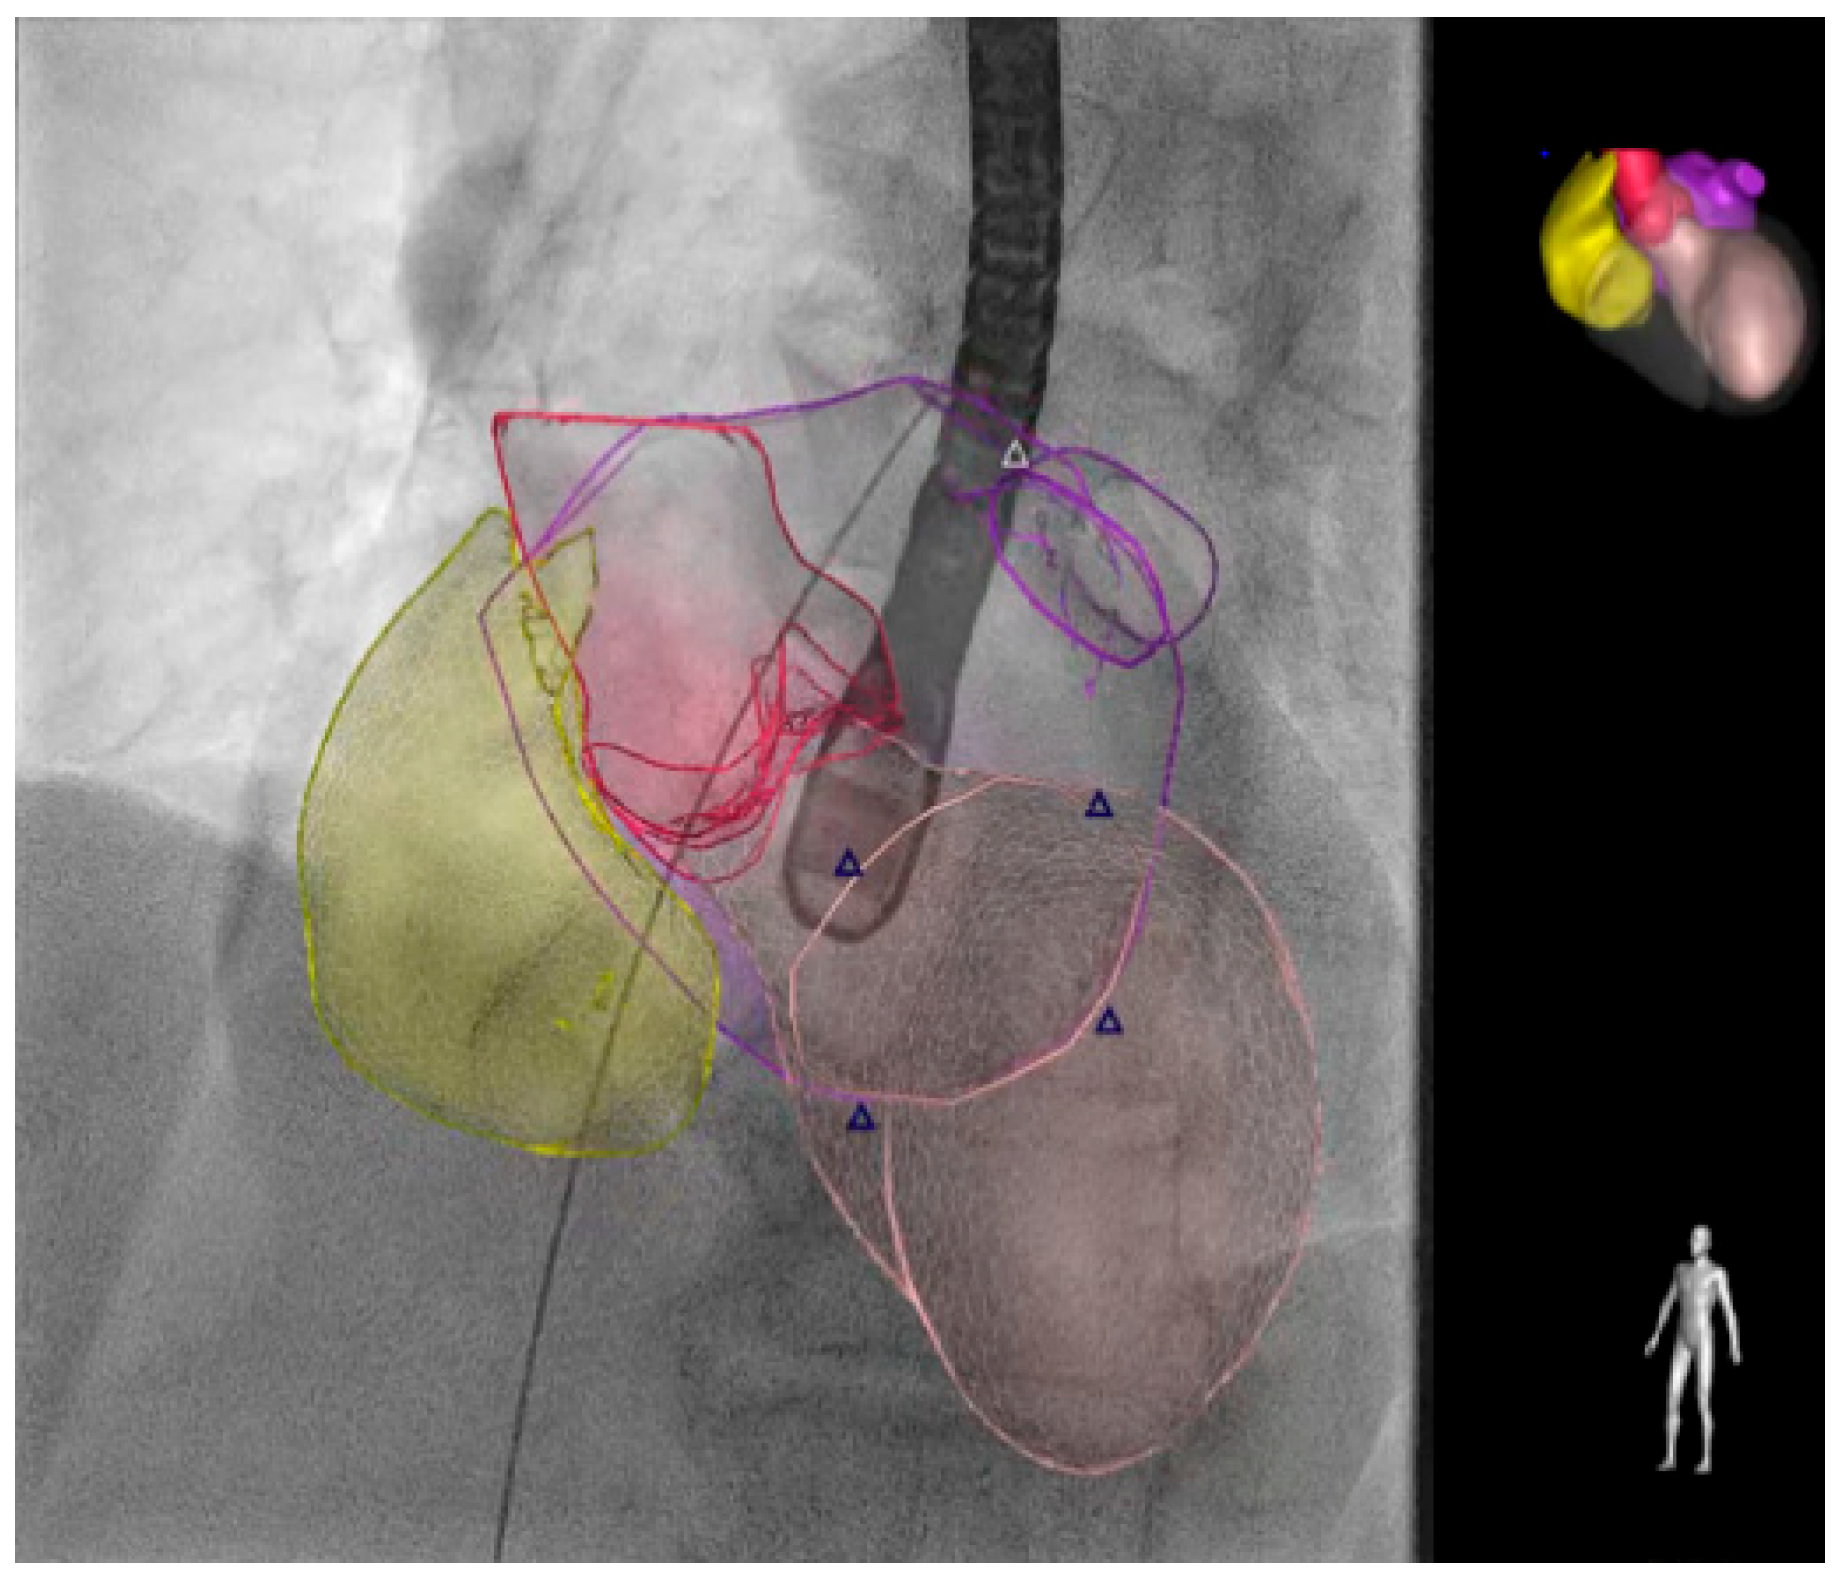

When alternatives are unavailable, fusion imaging (Figure 3) and transthoracic echocardiography may be used as an alternative to traditional TEE [65,66].

Figure 3.

The EchoNavigator® (Philips Medical System, Andover, MA, USA) live image guidance. The smart fusion technology simplifies visualization by fusing real-time X-rays and live echo. EchoNavigator may give interventionalists a supportive anatomical understanding and smooth guidance during structural heart disease interventions to reduce the time undergoing TEE. The different colors distinguish various cardiac structures, with the triangles indicating the position of the mitral valve. The right atrium is shown in yellow, the aorta in magenta, the left ventricle in pink, and the left atrium in purple as indicated in the cartoon in the top right. TEE: transesophageal echocardiography.